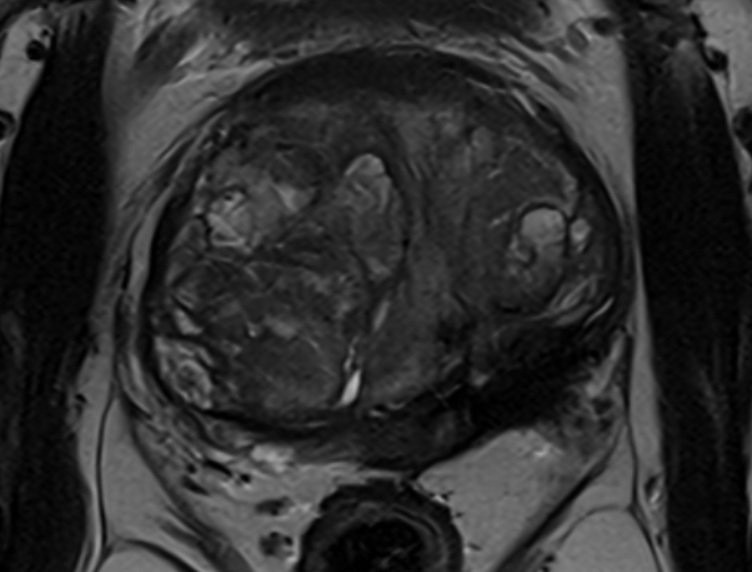

MRI 6 months post-treatment. The cancerous tissue is replaced with fibrosis (scar tissue), with no new pathology identified.